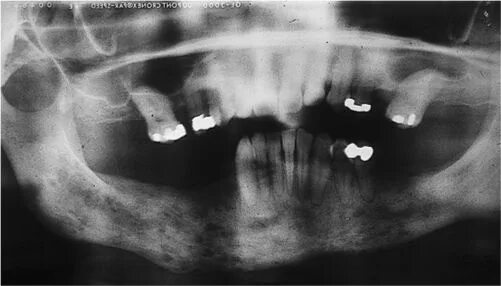

Одонтогенный остеомиелит челюсти. остеомиелит верх челюсти. хронический остеомиелит челюсти снимок. одонтогенного остеомиелита челюстей.

Одонтогенного остеомиелита. одонтогенный остеомиелит нижнечелюстной. остеомиелит верхней челюсти кт. острый остеомиелит верхней челюсти.

Подострая одонтогенного остеомиелита.. одонтогенный остеомиелит рентген. остеомиелит челюсти рентген. одонтогенный остеомиелит челюсти рентген.

Одонтогенный остеомиелит рентген. хронический остеомиелит челюсти. клиника острого остеомиелита нижней челюсти. муфтообразный инфильтрат.